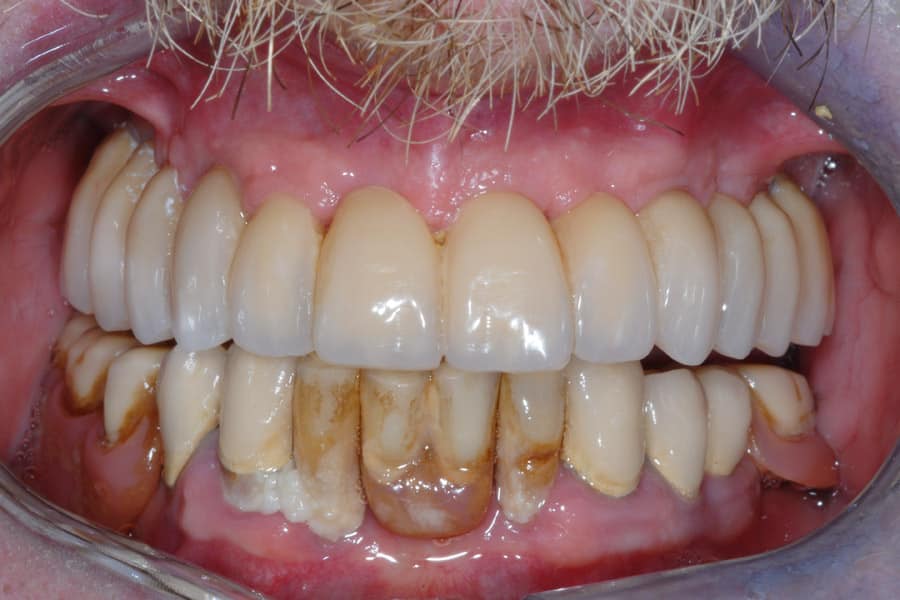

Il caso di Marco dimostra come la tecnologia moderna possa fare la differenza in odontoiatria. L’implantologia computer dinamica ci ha permesso di trovare osso utile dove sembrava non esserci, evitando al paziente dolorosi interventi di innesto osseo e riducendo drasticamente i tempi di guarigione.

Grazie a un approccio mini-invasivo, Marco ha ritrovato un sorriso stabile e sicuro, con denti fissi che emergono in modo armonioso dalle sue gengive naturali, rispettando a pieno le sue richieste estetiche e funzionali.

Visto l’ottimo risultato ottenuto nell’arcata superiore e il rapido recupero, ora Marco è pronto e sereno per procedere con l’intervento anche nella parte inferiore.